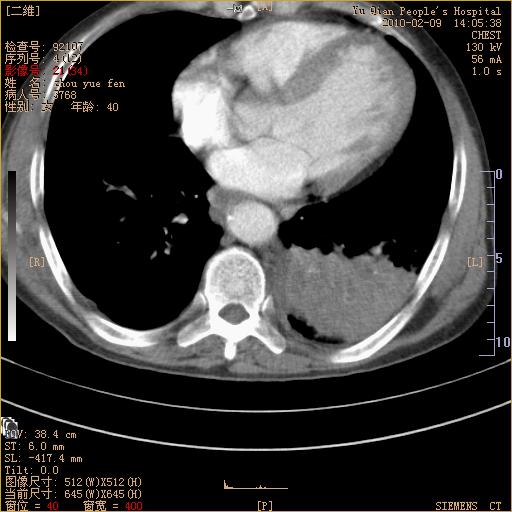

男性,73岁,咳嗽咳血数天,诊为肺ca伴左肺下叶后段阻塞性炎症、肺不张妥否?

左下肺中央型肺癌伴结段形肺不张,左侧胸腔积液,纵隔内见部分增大淋巴结(反应性增生或转移)

左下基底干支气管明显变窄。

左肺下叶基底段支气管狭窄,左肺门增大,左肺下叶团片状病灶。中心型肺癌伴柱塞性炎症可能大,建议支气管镜检查。

左下肺中央型肺癌伴节段性肺不张,左侧胸腔积液,纵隔内见肿大淋巴结

左下基底段支气管变窄。建议进一步纤支镜检查。

1、左肺下叶后基地段肺癌伴阻塞性炎症,左下肺门淋巴结转移。2、左侧胸腔积液。